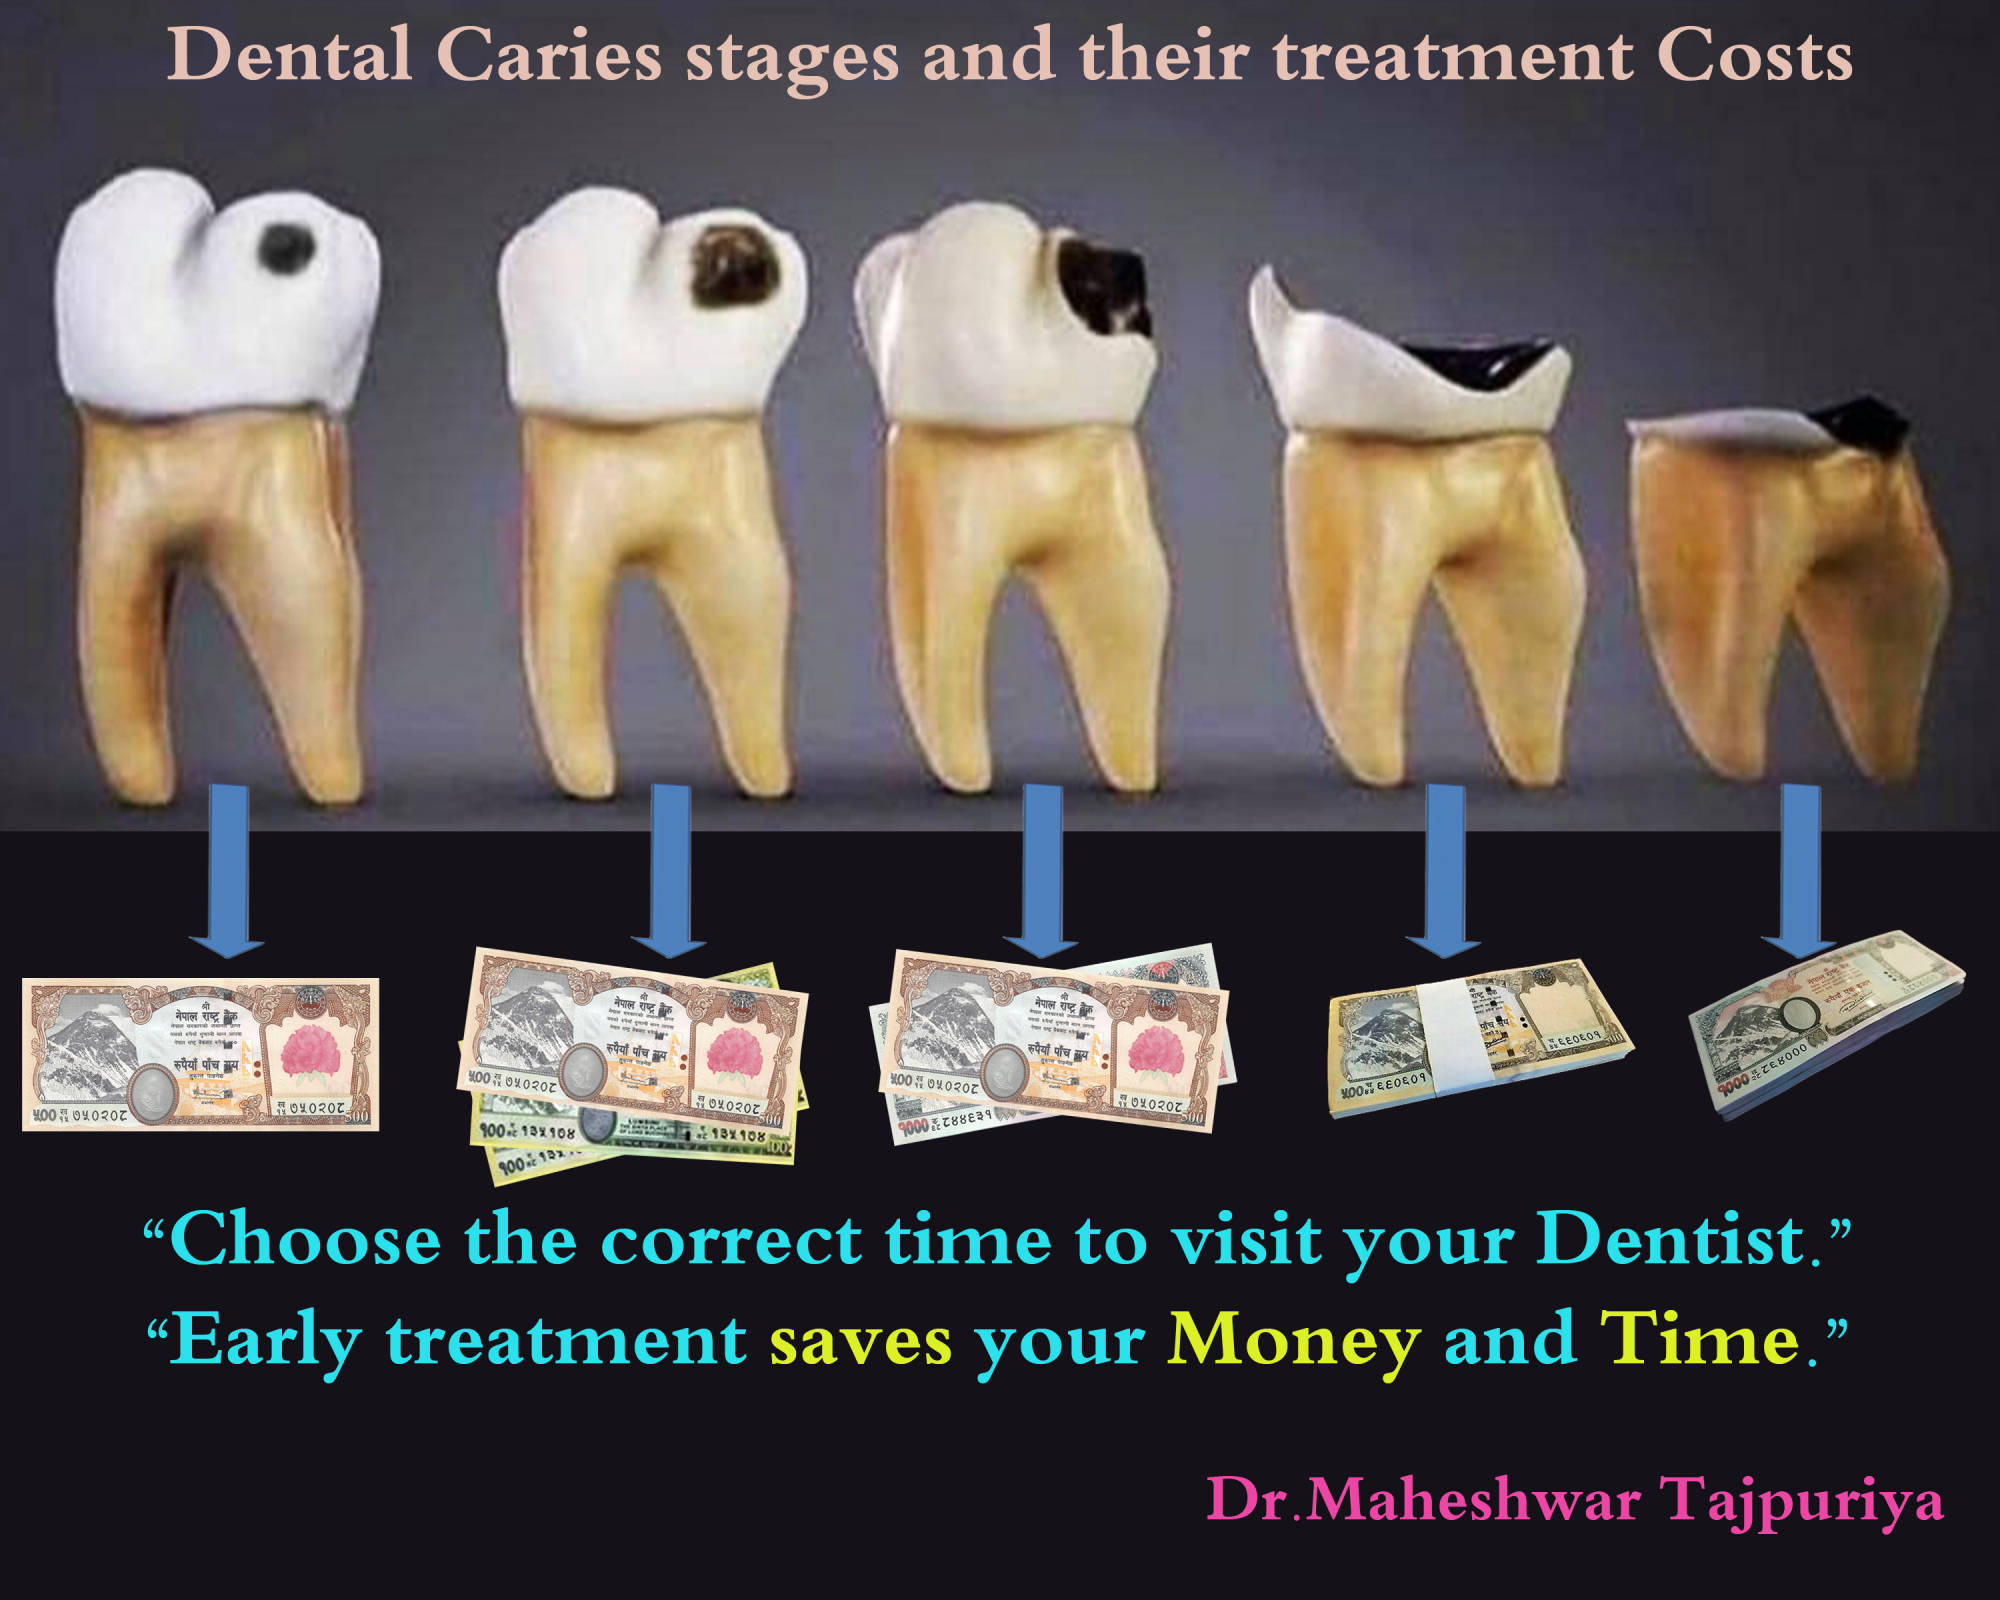

Bite Injury Dental Treatment & Cost

Dental Treatment & Cost Dental Stomattis